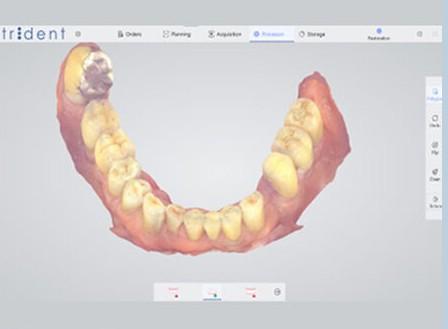

Elite dental as har inngått samarbeide med Italienske Trident.

Trident er et italiensk selskap som spesialiserer seg på produksjon av radiologiutstyr for dentalsektoren. Grunnlagt i Milano av Giorgio Rizzo, som viet sin karriere til dentalindustrien siden 1970;

Selskapet har i dag et høyt kvalifisert team, spesialiserte leverandører, unge designere og moderne produksjonsteknologi, noe som gjør Trident til et moderne firma som er i stand til å svare på forventningene til markedet ved å tilby praktiske, effektive løsninger for alle fagfolk i odontologisektoren.

100 % laget i Italia

Vi hjelper din klinikk med å starte opp med 3D printing og lage egne print- løsninger som du kan tilby dine pasienter.

Bittskinner

Kroner

Midlertidige kroner

Aligners

Egen Resin

Printere

Skannere

Design (eget LAB)

In house løsninger

Vi er de eneste som ikke selger en dyr og dårlig løsning for din klinikk, men et alternativ for deg å komme i gang med egen produksjon til RIKTIG PRIS

Ta kontakt for løsninger..